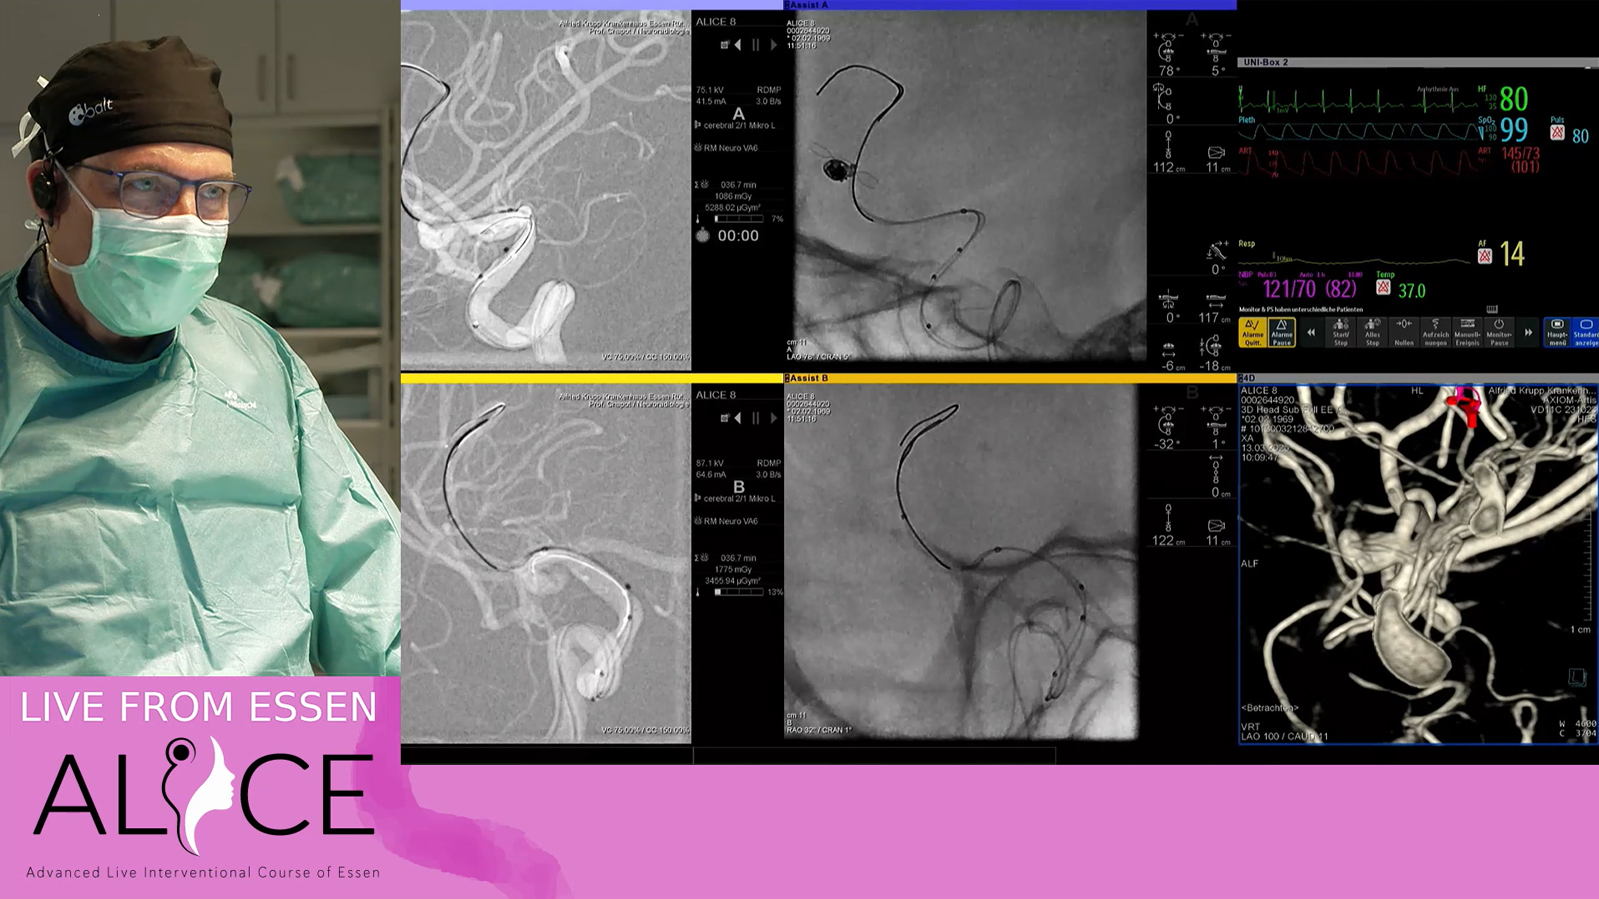

Giant fusiform basilar aneurysm treated by Stenting with Rex and occlusion of V4 on one side

Giant aneurysm of extradural ICA treated by antegrade telescopic pipelines